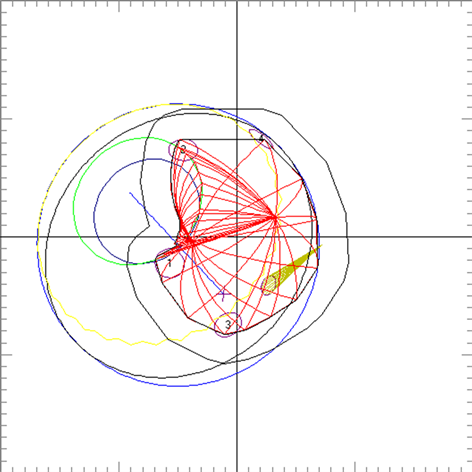

Clinical relevance of the extended distal range in silicone was studied for impact in EYEPLAN treatment planning software, including cases in which tumors were in close proximity to the optic disc/nerve and macula as well as cases in which anterior ciliary body tumors were treated. To demonstrate the necessity of the dosimetry measurement in silicone oil, we present an example of a patient with a ciliary body tumor in the right eye that is relatively amelanotic and involves the iris root but does not involve the angle. The dimension of the tumor is 13 × 8 × 8.7 mm3 (tumor height of 8.7 mm). Figure 5(a) shows the beam’s-eye-view (BEV) of the treatment plan, using gaze direction having polar and azimuth angle of (30˚, 135˚). The patient is looking towards the upper right-hand corner of the box (up and out). The range of the beam is 14.7 mm and SOBP is 16 mm. The aperture contour around the tumor represents the 50% isodose line. The optic nerve and macula are behind the tumor and receiving no proton dose, while some portion of the lens is within the 50% isodose line. This can be clearly seen from Figure 5(b) which shows the treatment plan in the lateral view. Figure 6(a) shows the dose distribution in the fundus view for a normal eye and figure 6(b) shows the dose distribution in the fundus view for a silicone oil filled eye, with adjusted proton range. Figure 7(a) and Figure 7(b) are the respective dose volume histograms (DVHs) for the two scenarios of a normal water-equivalent eye (7a) and a silicone-filled eye with potential proton range impact (7b). In this case as seen from Figure 6(a) and Figure 7(a), optic disc, macula and optic nerve gets 0 dose in the normal eye. If the eye were to be filled with silicone oil, the range of the beam would increase by 2mm. In that case as seen from Figure 6(b) and Figure 7(b), the dose to 50% area of the disc would increase by 50% of the total dose (i.e. 28 GyE in this simulation). A length of 0.4 mm of the optic nerve would receive 50% of the total dose (Figure 7(b)) as compared to the treatment plan if the eye is filled with water (Figure 7(a)). The doses to the structures of the eye in two scenarios are summarized in Table 3.

Figure 5. (a) The illustration of the treatment of uveal melanoma of the right eye in beam’s-eye-view using gaze direction having polar and azimuth angle of (30˚, 135˚). The patient is looking towards the upper right-hand corner of the box (up and out). The aperture contour around the tumor represents the 50% isodose line. The optic nerve and macula are posterior to the tumor, while a portion of the lens is in the field. (b) Shows the treatment plan in the transverse plane. The optic nerve and macula are estimated at 7 mm and 10 mm from the tumor.